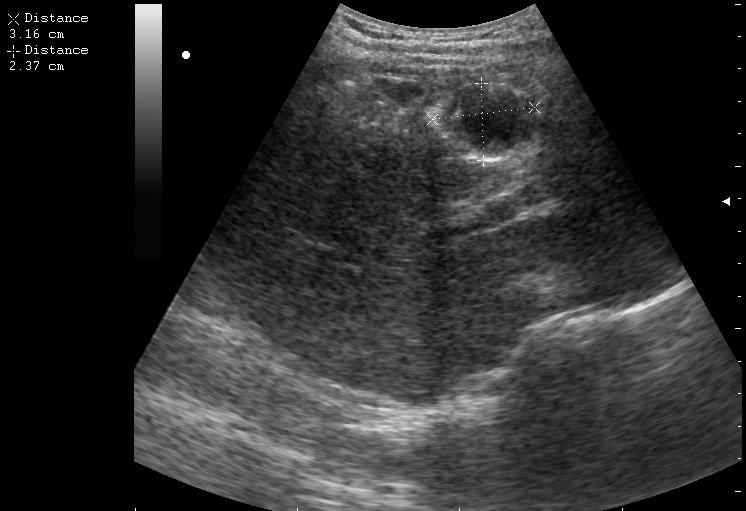

абсцесс передней брюшной стенки (через 2 недели п.о.)

нагноение остаточной полости